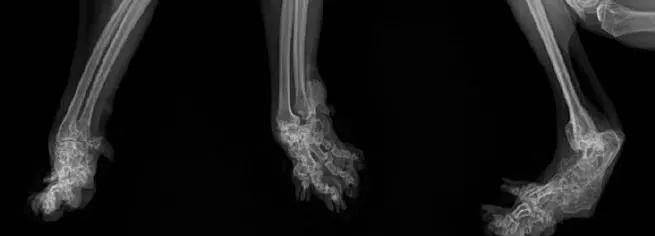

猫爪X光片,狗爪x光片

周扬青呼吁别养折耳猫!看得见的乖萌,看不见的折磨

猫爪到底有多萌?拍个x光也能融化少女心,网友:美到骨子里

猫爪x光照片,连小骨头都这么可爱,网友:心都被萌化了

狗爪x光片

猫咪正常爪子的X光片

正常猫爪x光图片